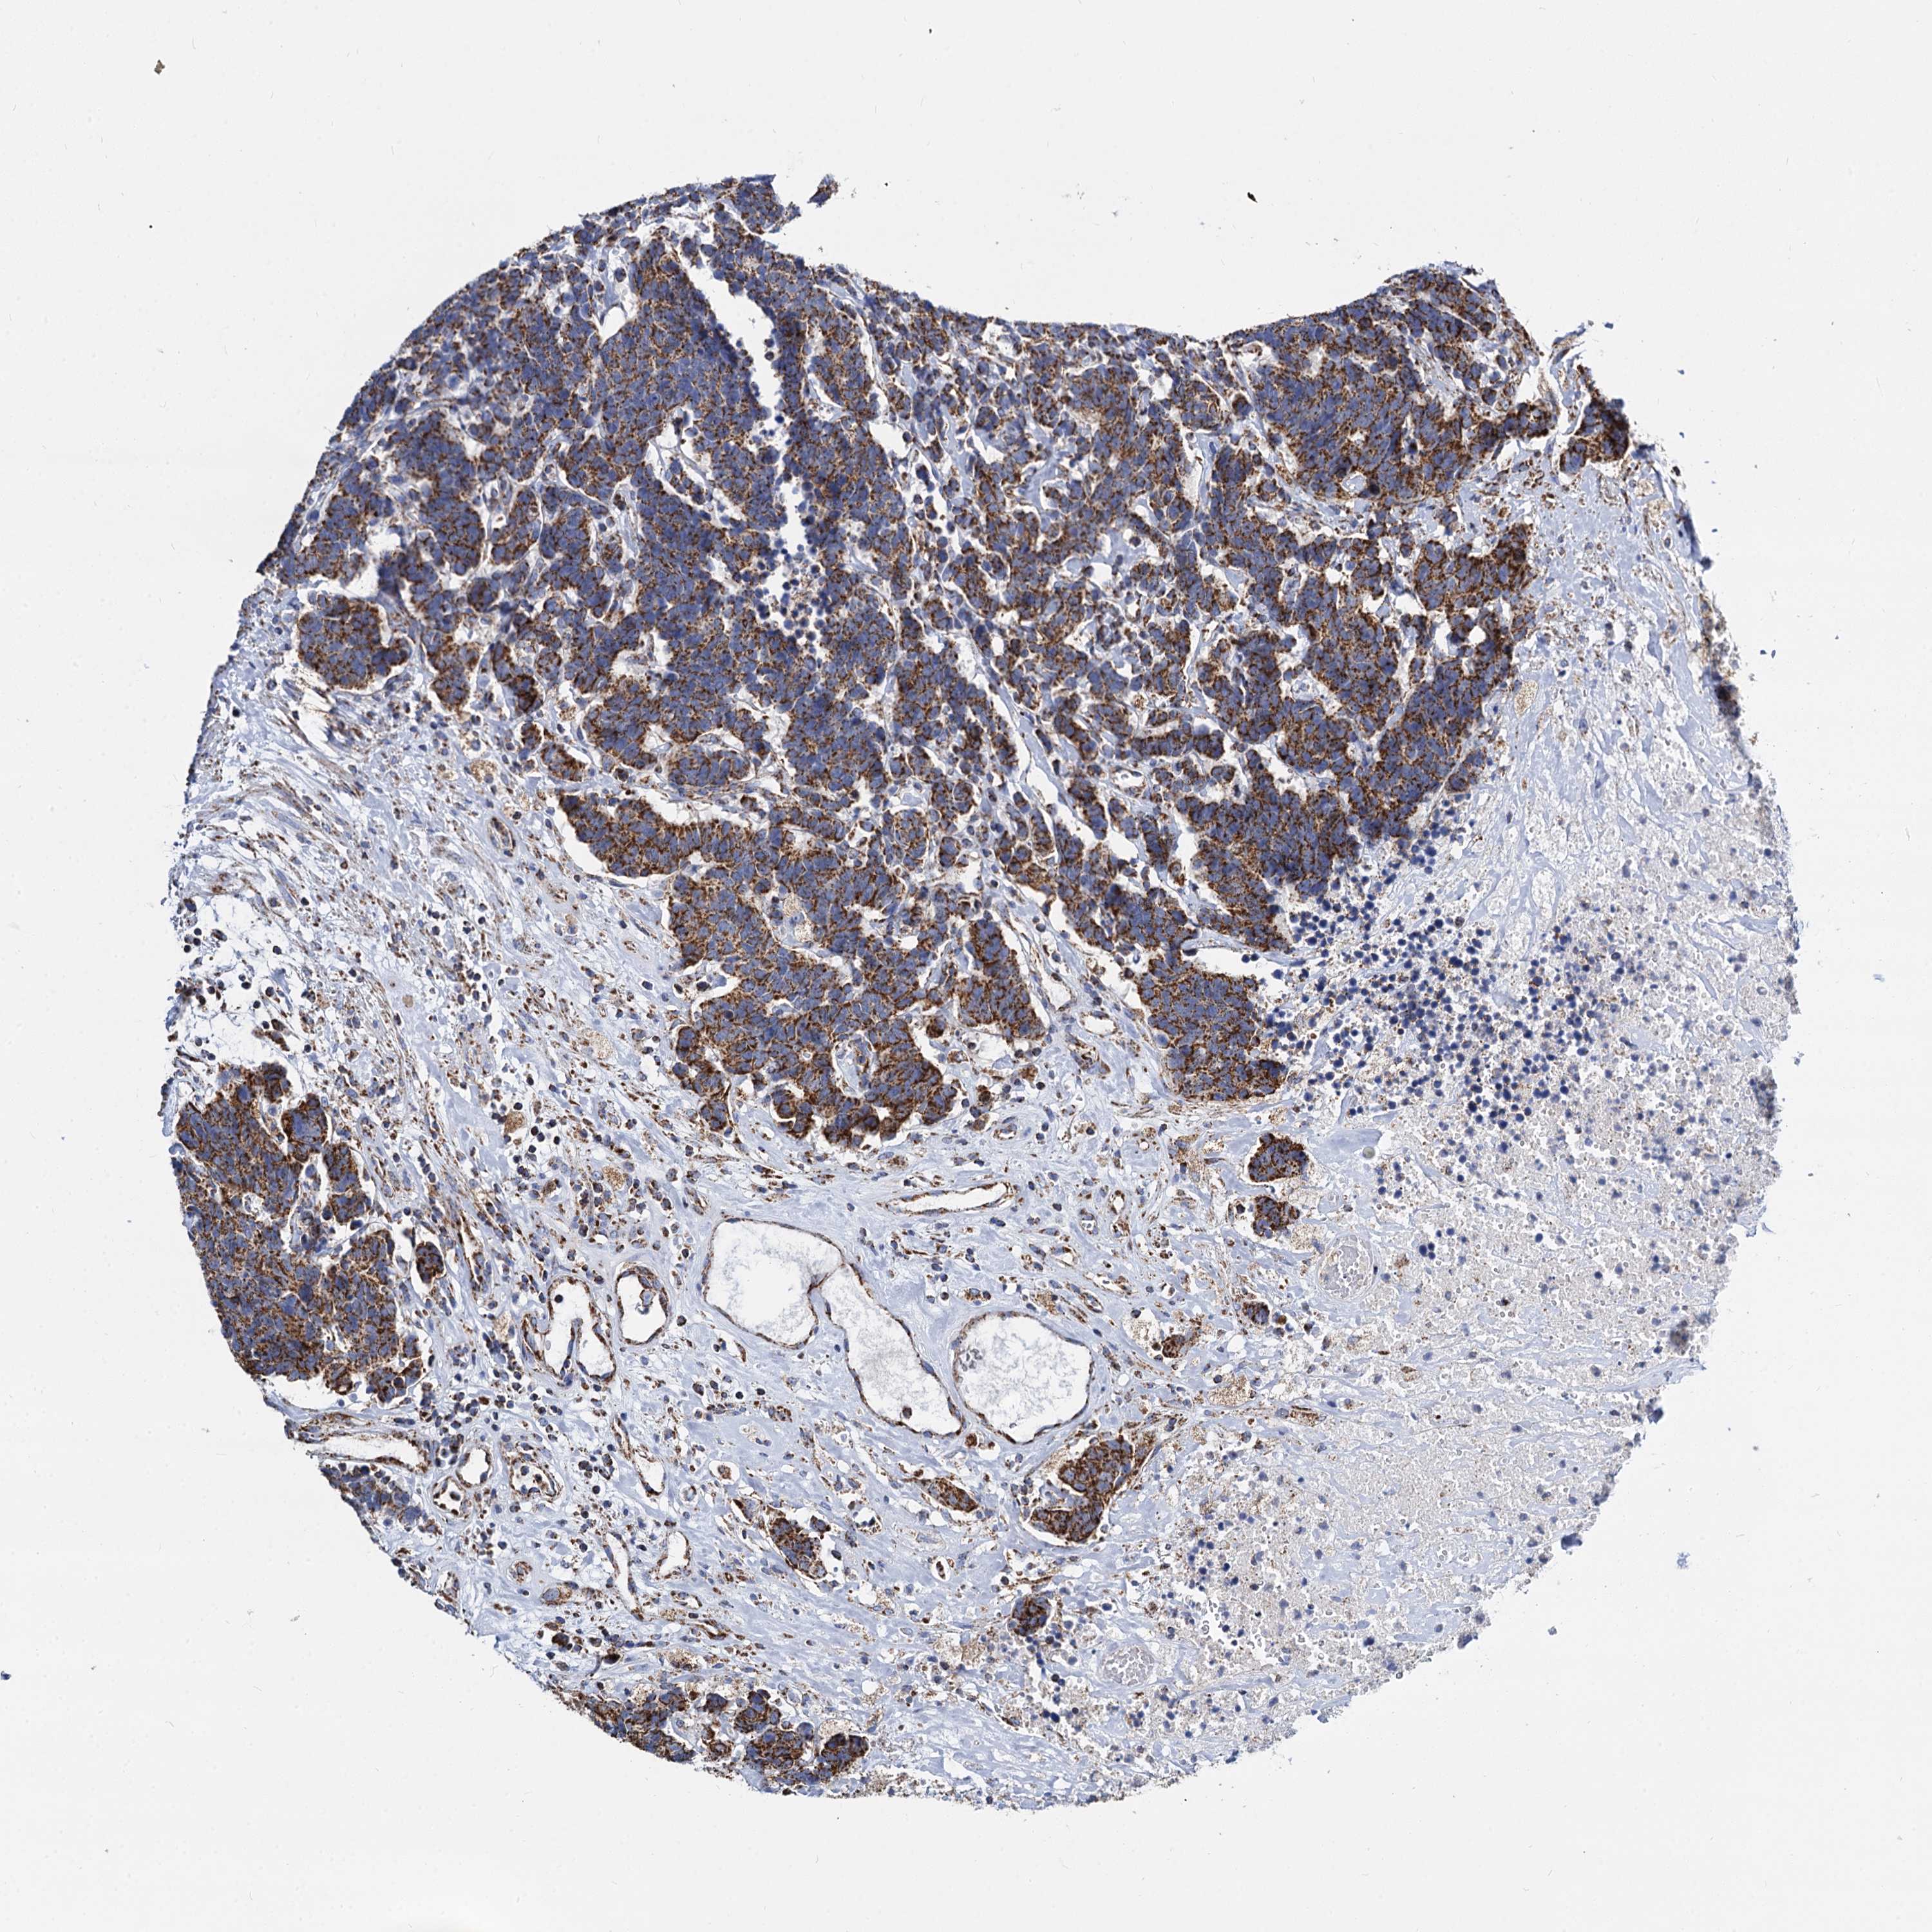

CARCINOID - Protein expressioni

A mouse-over function shows sample information and annotation data. Click on an image to view it in a full screen mode. Samples can be filtered based on level of antibody staining by selecting one or several of the following categories: high, medium, low and not detected. The assay and annotation is described here.

Antibody stainingi

Antibody staining in the annotated cell types in the current human tissue is reported as not detected, low, medium, or high, based on conventional immunohistochemistry profiling in selected tissues. This score is based on the combination of the staining intensity and fraction of stained cells.

Each image is clickable and will lead to virtual microscopy that enables deeper exploration of all samples and also displays staining intensity scores, fraction scores and subcellular localization as well as patient and tissue information for each sample.

Antibody HPA039946

Staining

High

Medium

Low

Not detected

Intensity

Strong

Moderate

Weak

Negative

Quantity

>75%

75%-25%

<25%

None

Location

Nuclear

Cytoplasmic/membranous

Cytoplasmic/membranous,nuclear

Carcinoid, malignant, NOS

Carcinoma, NOS